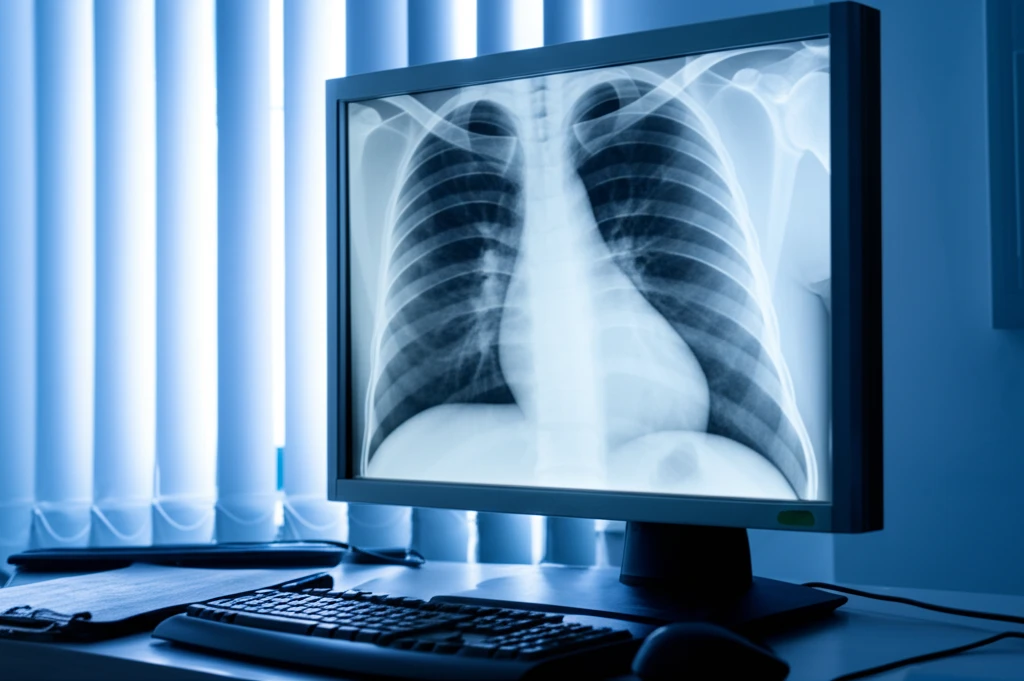

기관지염 진단은 주로 환자의 증상과 병력을 바탕으로 이루어집니다. 의사는 청진기를 사용하여 폐의 소리를 듣고, 다음과 같은 추가 검사를 시행할 수 있습니다.

- 흉부 X선 검사: 폐렴과 같은 다른 질환을 배제하기 위해 필요합니다.